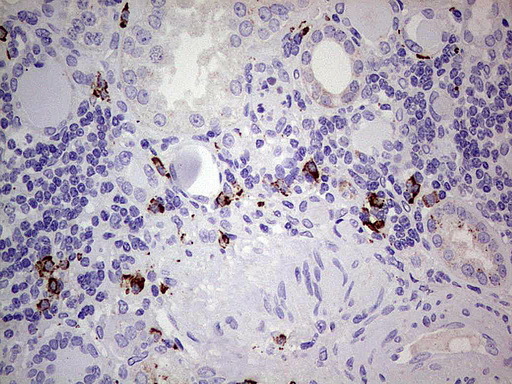

- Submitted by

- OriGene (provider)

- Main image

- Experimental details

- Immunohistochemical staining of paraffin-embedded Human melanoma tissue using anti-GLI1 mouse monoclonal antibody. (UM800063; heat-induced epitope retrieval by 1 mM EDTA in 10mM Tris, pH8.0, 120C for 3min)

- Validation comment

- IHC